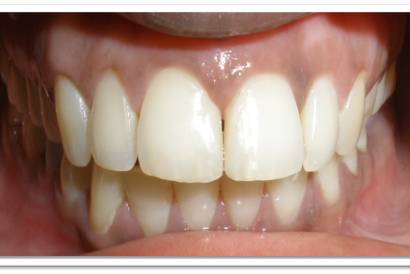

Before

After